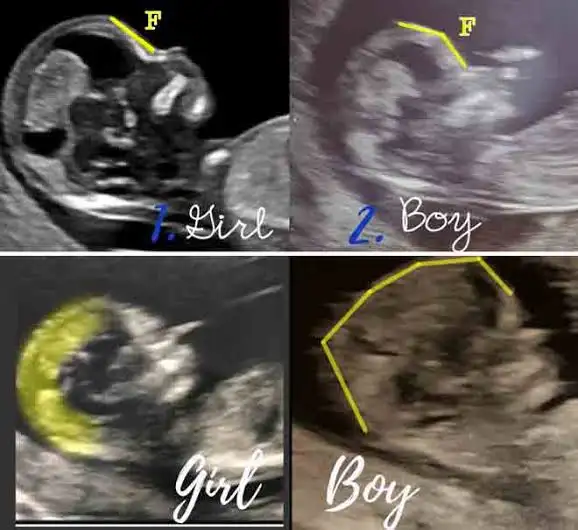

Maşallah minnoşaKızlar ay o kadar heyecanlandım ki başım dönüyordu içeri girdiğimde sanki :)) elleri kolları oynuyordu hareket ediyordu o halini görünce ay o kadar duygulandım ki anlatamamdoktor yüzde 95 kız dedi